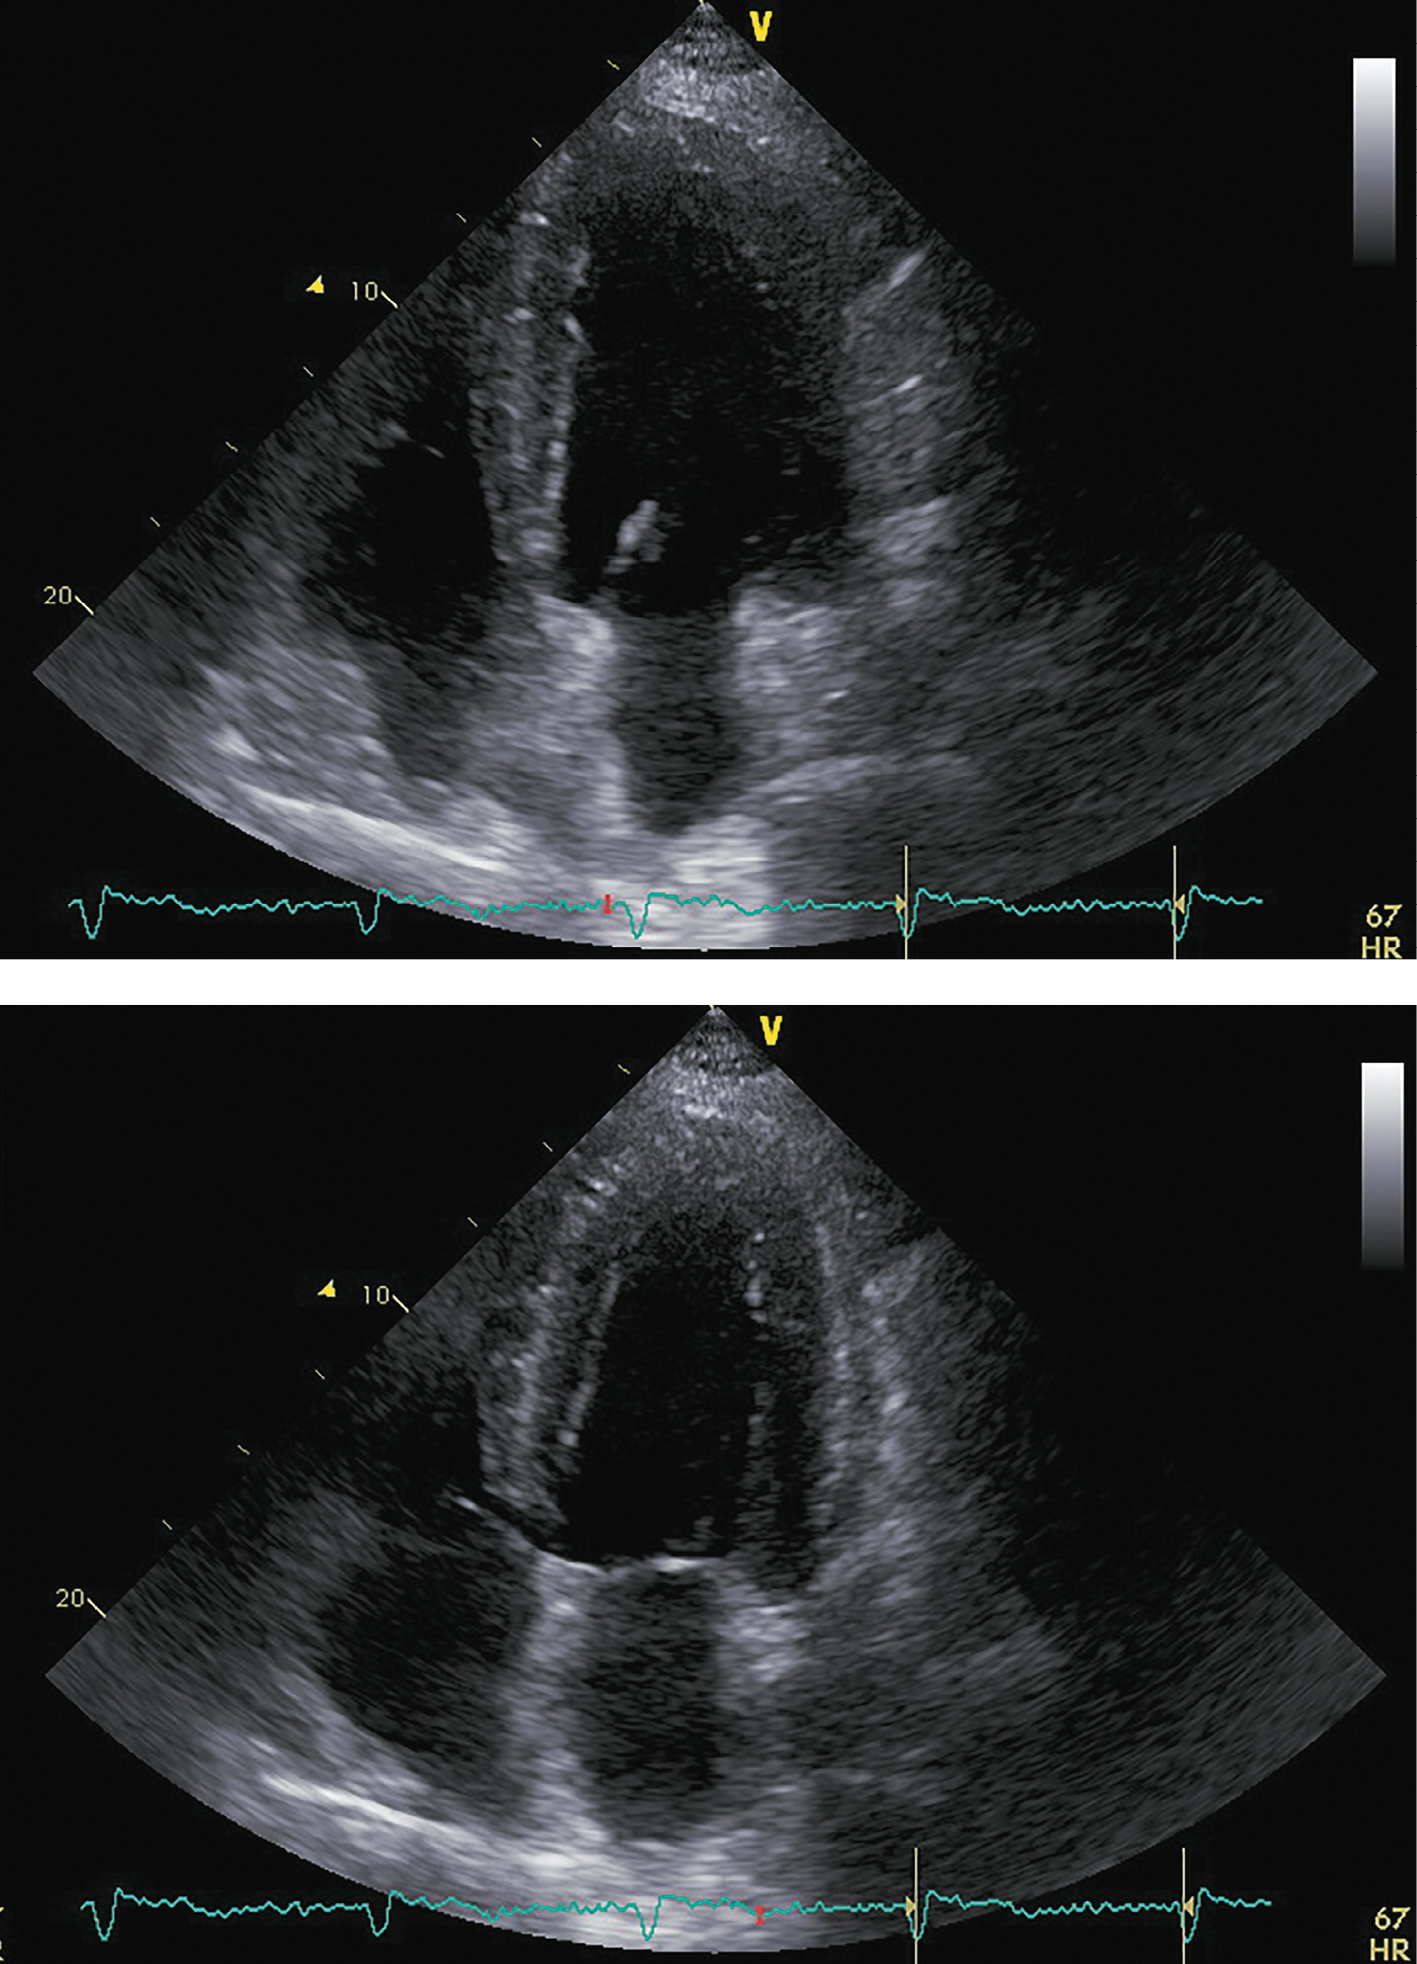

При госпитализации в октябре 2017 г. для проведения оперативного вмешательства было отмечено прогрессирование симптомов ХСН: выраженное снижение толерантности к нагрузкам с развитием одышки при минимальной физической активности, ночное ортопноэ, выраженные периферические отеки, физикальные симптомы легочного застоя (влажные хрипы в нижних отделах легких), гепатомегалия. Пациент сообщил, что получал предписанную терапию в полном объеме. На ЭХОКГ были отмечены выраженная дилатация левых камер сердца, признаки гипертрофии ЛЖ, диффузный гипокинез ЛЖ с выраженным снижением ФВ ЛЖ (19%), рестриктивная диастолическая дисфункция ЛЖ (рис. 4; табл. 2). Таким образом, несмотря на проводимую терапию, отмечено прогрессирование симптомов ХСН с дальнейшим снижением ФВ ЛЖ и развитием выраженной диастолической дисфункции. Потребовалась модификация терапии: назначение внутривенных диуретиков (фуросемид 80 мг) в течение 5 дней. После внутривенной диуретической терапии исчезли эпизоды ночного ортопноэ и физикальная симптоматика легочного застоя, существенно уменьшились периферические отеки. Постоянная пероральная терапия была модифицирована: добавлены БМКК, а также увеличены дозы пероральных диуретиков, ИАПФ, бетаАБ и кетоконазола (рис. 1). Операция была отложена на один месяц.

Рисунок 4. ЭХОКГ, 1 месяц до аденомэктомии.

Примечание: верхушечная 4-камерная позиция (сверху представлен кадр в диастолу, снизу — в систолу).

Таблица 2. ЭХОКГ-показатели, 1 месяц до аденомэктомии

| Показатель | Значение/индекс |

| Объем левого предсердия | 135 мл/54 мл/м² |

| Передне-задний размер левого желудочка | 7,20 см/2,89 см/м² |

| Конечно-диастолический объем левого желудочка | 369 мл/148 мл/м² |

| Конечно-систолический объем левого желудочка | 297 мл/119 мл/м² |

| Локальная кинетика левого желудочка | диффузный гипокинез |

| Фракция выброса левого желудочка (усреднение по 4- и 2-камерным верхушечным позициям) | 19% |

| Диастолическая функция левого желудочка | градация III, рестриктивный тип |

| Конечно-диастолическая площадь правого желудочка | 27 см²/10,8 см²/м² |

| Конечно-систолическая площадь правого желудочка | 13,5 см²/5,4 см/м² |

| Фракция систолического уменьшения площади | 50% |

| Расчетное систолическое давление в легочной артерии | 50 мм рт.ст. |